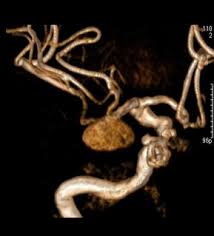

"MRA(Magnetic Resonance Angiography, 자기공명 혈관촬영)"는 MRI를 기반으로 혈관 구조를 영상화한 검사입니다.

- 주요 특징: 동맥, 정맥, 혈관 협착, 동맥류 등 혈관 상태 평가에 특화

MRA는 심혈관 질환, 뇌혈관 질환, 말초 혈관 질환 등 혈관 이상 진단에 특히 유용합니다.

(2) MRA 적응증

- 뇌혈관 질환: 동맥류, 뇌경색 위험 평가